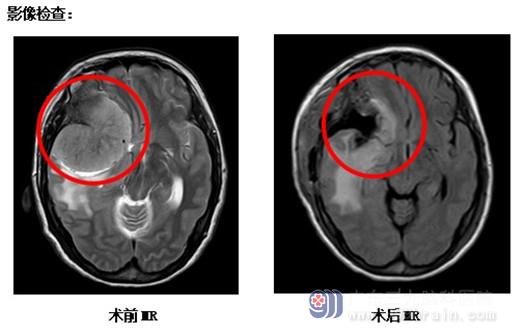

入院后张阿姨由李兴可医生经管,李医生看了张阿姨拍的检查片子解释道:张阿姨的右侧额颞部有一个巨大占位性病变,有6x6x6cm大小,考虑蝶骨嵴脑膜瘤可能性大,手术指征明确。完善相关检查后,外十科团队于5月15号在全麻下行右侧额颞部巨大占位性病变切除术,手术很顺利,张阿姨恢复良好,右眼也能看到手指了,张阿姨已于日前高兴出院。